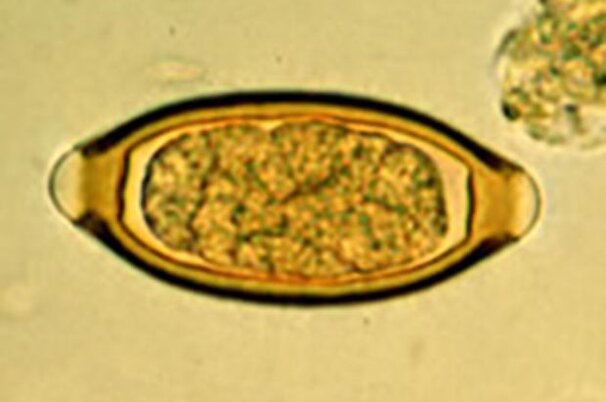

Wirkstoff aus Tiermedizin bekämpft Würmer bei Kindern